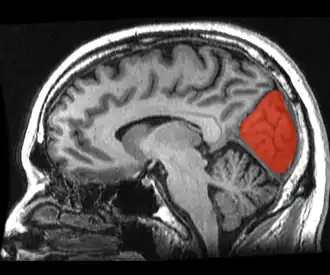

![]() Sagittal MRI slice with the cuneus and lingual gyrus shown in red. | |